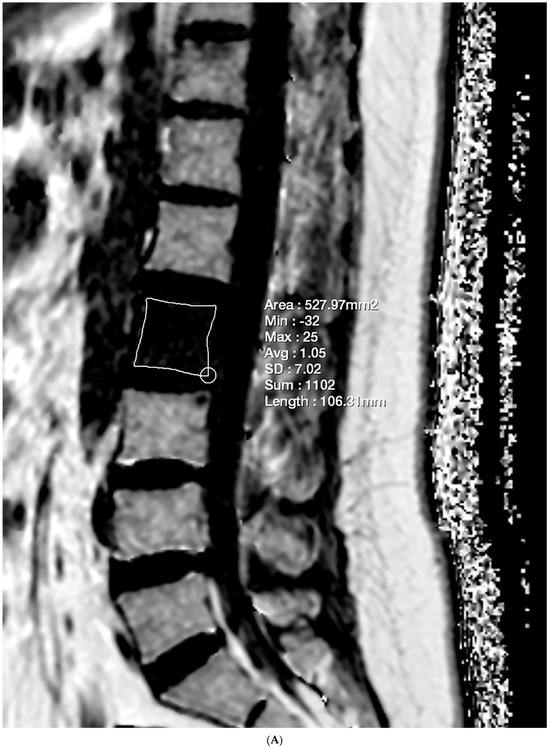

Lesions meeting the criteria of the first and either the second or third condition were included in the evaluation. The imaging criterion standards were determined through a consensus reading by two researchers. Subsequently, the lesions were classified as either benign or malignant. Another researcher manually delineated the ROI on FF maps and sagittal T1-weighted images for each selected lesion to ensure maximum coverage, enabling the calculation of FF and VBQ scores (Figure 2).

Figure 2.

Lumbar spine MRI of a 48-year-old female with multiple bone metastases from adenoid cystic carcinoma of the parotid gland. (A) GRE-based CSE-MRI reveals an FF of 1.05% in the metastatic lesion of the L2 vertebral body. (B) On SE-based CSE-MRI, the FF of the corresponding lesion was 7.30%. The number in the figure indicate the ROI numbering in the EXPRESS program. (C) Multiple bone metastases are observed in the T11, L2, and L3 vertebral bodies on the T1-weighted image. The VBQ score for the L2 vertebral body lesion was 0.96.

FF and the VBQ score for each lesion were presented in Figure 4. Benign lesions exhibited an FFGRE of 44.11 ± 34.29%, while malignant lesions showed 0.91 ± 0.86%. The two groups showed statistically significant differences (p = 0.004). Benign lesions were statistically significantly higher than malignant lesions in FFSE (54.46 ± 28.36% vs. 9.99 ± 5.32%; p = 0.007). However, the difference in VBQ score was not statistically significant (2.48 ± 1.18 vs. 1.36 ± 0.36; p = 0.089).